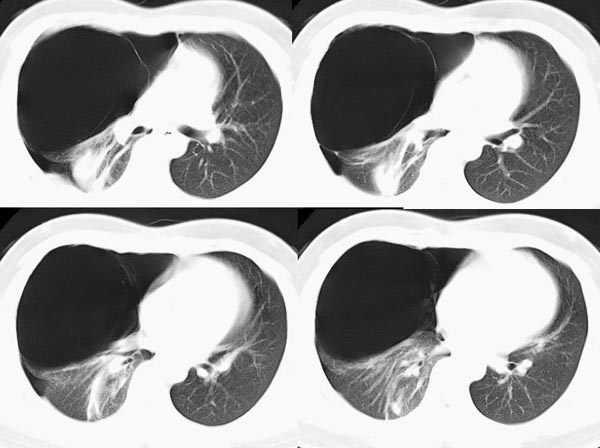

m21y既往体健,否认结核、支扩等病史;1周前患上感,无明显咳嗽,自觉无明显不适。单位体检透视时发现右侧液气胸!cr及ct如下(肺组织窗:l:-598hu w:1132hu):请大家会诊!!

右侧巨大含气囊性病变,壁薄、光整、其外侧见气体。右肺压迫性肺不张、胸腔内见少量积液。纵隔向左侧移位。左肺未见异常。诊断:1.右侧含气肺囊肿(先天性)。2.右侧液气胸。(少量液体)3.右肺压迫性肺不张。我也遇见一例这样的病人。女性。股骨外伤就诊。常规胸片发现右侧囊性病变。